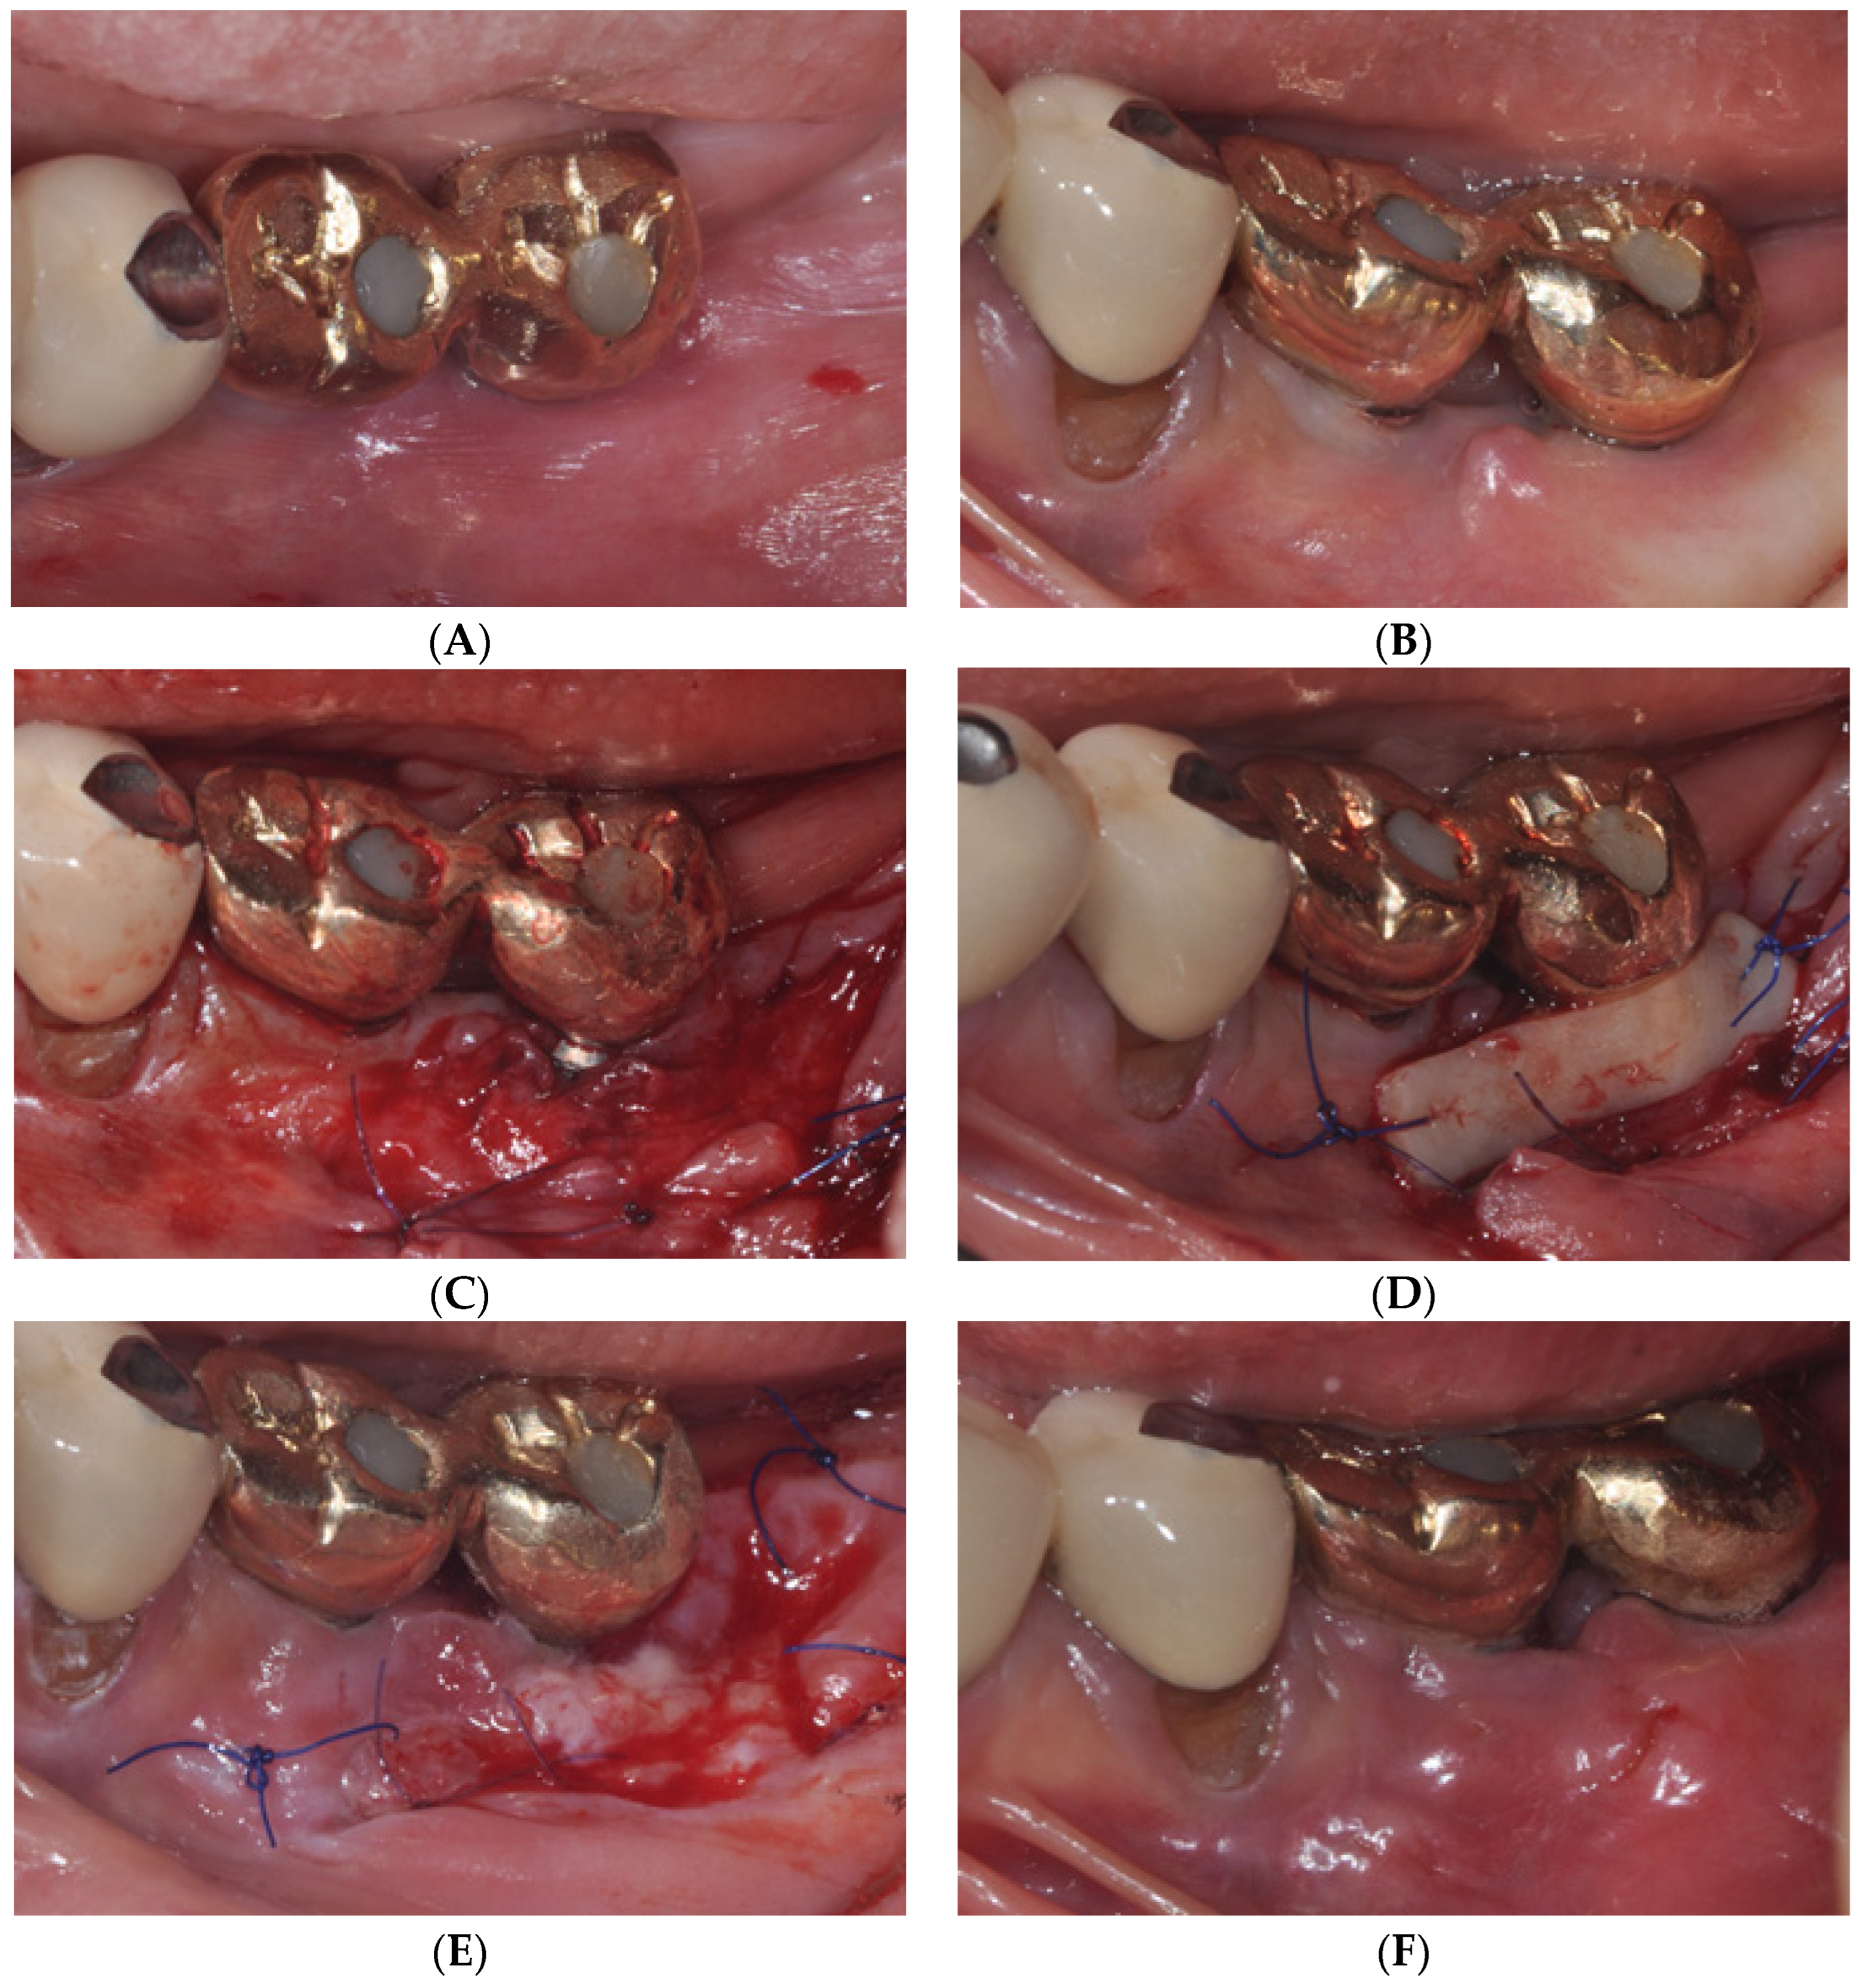

2.1. Surgical Procedures of Er:YAG Laser-Assisted Periosteal Fenestration (LA-PF)

2.2. Case